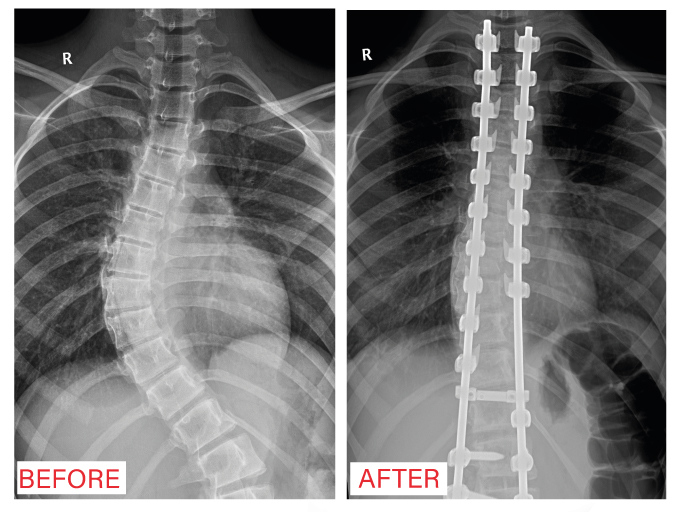

After doing the necessary x-rays, it was found that the patient suffers from a congenital deformity in the shape of the spine in the form of an S-shaped warp in the thoracic and lumbar vertebrae.

After discussing the case with the medical team, the scoliosis repair surgery was performed by fixing the vertebrae with stents and screws under general anesthesia for the girl with no medical complications.

The patient was followed up for 3 days in the hospital until her discharge in good health, where the warp was repaired and the shoulders were straightened, with no weakness in the limbs.